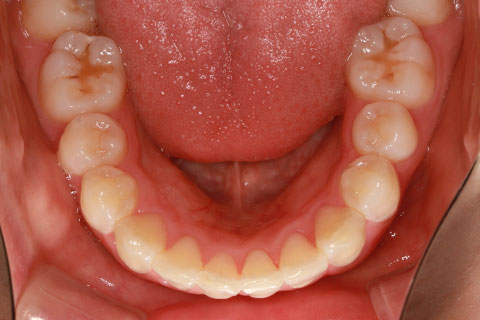

フルリンガル矯正2(上下の歯を舌側矯正で治療)

治療前

治療中

治療後

- 年齢・性別

- 42歳男性

- 治療期間

- 1年6ヶ月

- 抜歯

- なし

- 治療費

- 120万円(税込み)

- 備考

- マルチブラケットを用いた矯正治療

- 治療内容

- 反対咬合をフルリンガル矯正治療にて改善

- 施術の副作用(リスク)

- 表側矯正と比較して、歯根の角度を確立する「トルク」の力がかかりにくい。